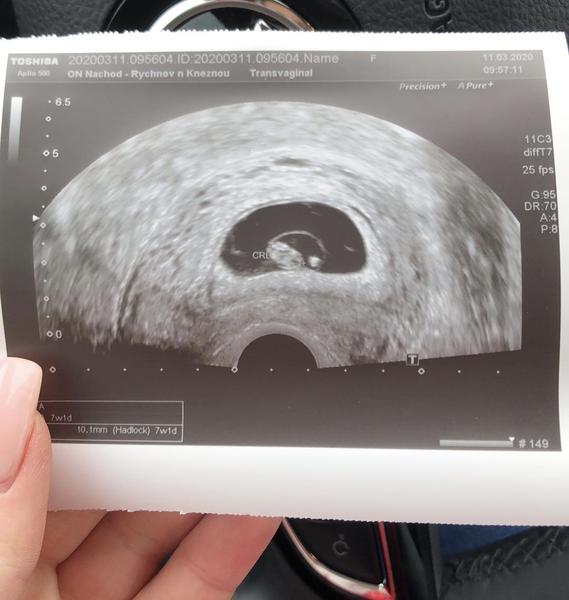

@radousekkk 7+1 dle utz, jinak poslední ms 7+4